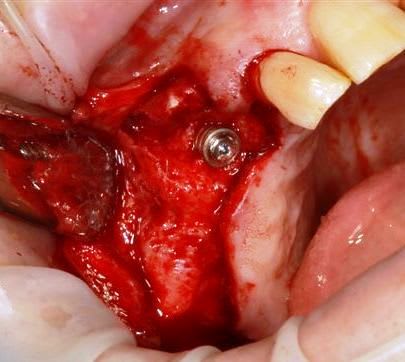

13 fenestration vestibulaire j'utilise la paroi palatine, lame N°15, spreader, expansion et pose d'un 40140

Puis 40120 en 15 avec léger SL, à l'ostéotome, et 40120 en 17.

modelage zone 13,finitions, mise en place du bloc osseux, qui sera soigneusement impacté (pas de vis) prélèvement d'un petit bloc triangulaire pour finir la fermeture, éponges de gelatemp, sutures.